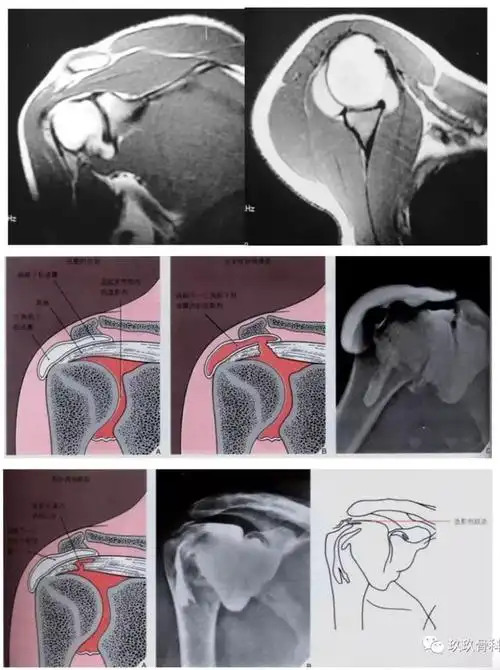

病例右肩关节损伤1例mr影像表现–影像ppt

肩关节肌腱病一文读懂肩袖损伤的磁共振分级

肩袖部分撕裂mri造影表现:韧带变细,其关节面缘见龛影形成,其诊断的

看完收藏了肩关节损伤的mri诊断